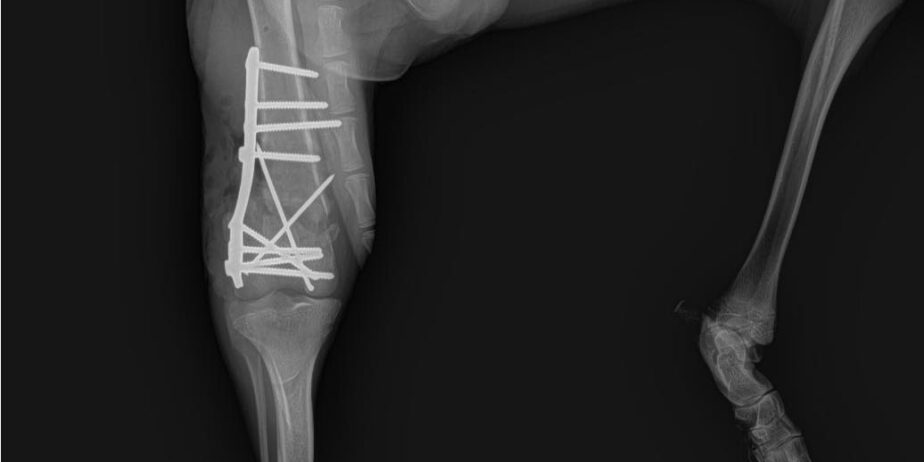

๐Ÿพ ๐Œ๐ˆ๐“๐’๐ˆ๐’ โ€“ ๐จ๐ฎ๐ซ ๐›๐ซ๐š๐ฏ๐ž, ๐ก๐š๐ฉ๐ฉ๐ฒ-๐ ๐จ-๐ฅ๐ฎ๐œ๐ค๐ฒ ๐›๐จ๐ฒ ๐ฅ๐จ๐จ๐ค๐ข๐ง๐  ๐Ÿ๐จ๐ซ ๐ก๐ข๐ฌ ๐Ÿ๐จ๐ซ๐ž๐ฏ๐ž๐ซ ๐Ÿ๐š๐ฆ๐ข๐ฅ๐ฒ ๐Ÿพ This handsome ๐€๐ซ๐ข๐ž๐ ๐ž๐จ๐ข๐ฌ ๐œ๐ซ๐จ๐ฌ๐ฌ, almost 1.5 years old, has come such a long way. ๐Ÿ’ช When Mitsis arrived to us back in June, he was limping badly โ€” X-rays revealed his bone was completely broken and dangling. ๐Ÿ’” But thanks to a skilled orthopedic surgeon (and lots of love!), he underwent a successful operation and began his healing journey. ๐Ÿฉบ (See X-rays) After months of rest and limited movement, Mitsis is now stretching his legs again โ€” literally! ๐Ÿ•๐Ÿ’จ Heโ€™s gaining strength every day, playing with his doggy friends, and showing everyone just how joyful and resilient he is. Mitsis is ๐Ÿ๐š๐ง๐ญ๐š๐ฌ๐ญ๐ข๐œ ๐ฐ๐ข๐ญ๐ก ๐จ๐ญ๐ก๐ž๐ซ ๐๐จ๐ ๐ฌ, loves having playmates, and equally adores ๐œ๐ฎ๐๐๐ฅ๐ž๐ฌ ๐Ÿ๐ซ๐จ๐ฆ ๐ก๐ข๐ฌ ๐ก๐ฎ๐ฆ๐š๐ง๐ฌ. Heโ€™s social, gentle, and full of love โ€” ready to bring happiness to his new home. โค๏ธ ๐ŸŽถMitsis even joined us at an event full of people, music, and excitement โ€” and he handled it like a pro! Nothing phased him; he stayed calm, friendly, and curious the entire time. ๐ŸŒŸ ๐Ÿก He can be adopted Cyprus or UK โธป ๐Ÿพ ฮœฮฏฯ„ฯƒฮทฯ‚ โ€“ ฯ„ฮฟ ฮณฮตฮฝฮฝฮฑฮฏฮฟ, ฯ‡ฮฑฯฮฟฯฮผฮตฮฝฮฟ ฮฑฮณฯŒฯฮน ฮผฮฑฯ‚ ฯ€ฮฟฯ… ฯˆฮฌฯ‡ฮฝฮตฮน ฯ„ฮทฮฝ ฯ€ฮฑฮฝฯ„ฮฟฯ„ฮนฮฝฮฎ ฯ„ฮฟฯ… ฮฟฮนฮบฮฟฮณฮญฮฝฮตฮนฮฑ! ๐Ÿพ ฮ‘ฯ…ฯ„ฯŒ ฯ„ฮฟ ฯ€ฮฑฮฝฮญฮผฮฟฯฯ†ฮฟ ๐€๐ซ๐ข๐ž๐ ๐ž๐จ๐ข๐ฌ ๐œ๐ซ๐จ๐ฌ๐ฌ, ฯƒฯ‡ฮตฮดฯŒฮฝ 1,5 ฮญฯ„ฮฟฯ…ฯ‚, ฮญฯ‡ฮตฮน ฮดฮนฮฑฮฝฯฯƒฮตฮน ฮผฮนฮฑ ฮฑฯ€ฮฏฯƒฯ„ฮตฯ…ฯ„ฮท ฮดฮนฮฑฮดฯฮฟฮผฮฎ. ๐Ÿ’ช ฮŒฯ„ฮฑฮฝ ฮฎฯฮธฮต ฯƒฮต ฮตฮผฮฌฯ‚ ฯƒฯ„ฮนฯ‚ ฮฑฯฯ‡ฮญฯ‚ ฯ„ฮฟฯ… ฮ™ฮฟฯ…ฮฝฮฏฮฟฯ…, ฮบฮฟฯ…ฯ„ฯƒฯŒฯ‚ โ€” ฮฟฮน ฮฑฮบฯ„ฮนฮฝฮฟฮณฯฮฑฯ†ฮฏฮตฯ‚ ฮญฮดฮตฮนฮพฮฑฮฝ ฯŒฯ„ฮน ฯ„ฮฟ ฮบฯŒฮบฮฑฮปฮฟ ฯ„ฮฟฯ… ฮฎฯ„ฮฑฮฝ ฯ„ฮตฮปฮตฮฏฯ‰ฯ‚ ฯƒฯ€ฮฑฯƒฮผฮญฮฝฮฟ ฮบฮฑฮน ฮบฯฮตฮผฯŒฯ„ฮฑฮฝ. ๐Ÿ’” ฮงฮฌฯฮท ฯŒฮผฯ‰ฯ‚ ฯƒฮต ฮญฮฝฮฑฮฝ ฮฟฯฮธฮฟฯ€ฮตฮดฮนฮบฯŒ (ฮบฮฑฮน ฮผฮต ฯ€ฮฟฮปฮปฮฎ ฮฑฮณฮฌฯ€ฮท), ฯ…ฯ€ฮฟฮฒฮปฮฎฮธฮทฮบฮต ฯƒฮต ฮตฯ€ฮนฯ„ฯ…ฯ‡ฮทฮผฮญฮฝฮท ฮตฯ€ฮญฮผฮฒฮฑฯƒฮท ฮบฮฑฮน ฮพฮตฮบฮฏฮฝฮทฯƒฮต ฯ„ฮฟ ฯ„ฮฑฮพฮฏฮดฮน ฯ„ฮทฯ‚ ฮฑฮฝฮฌฯฯฯ‰ฯƒฮฎฯ‚ ฯ„ฮฟฯ…. ๐Ÿฉบโœจ (ฮ”ฮตฮฏฯ„ฮต ฯ„ฮนฯ‚ ฮฑฮบฯ„ฮนฮฝฮฟฮณฯฮฑฯ†ฮฏฮตฯ‚) ฮœฮตฯ„ฮฌ ฮฑฯ€ฯŒ ฮผฮฎฮฝฮตฯ‚ ฯ€ฮตฯฮนฮฟฯฮนฯƒฮผฮฟฯ ฮบฮฑฮน ฮพฮตฮบฮฟฯฯฮฑฯƒฮทฯ‚, ฮฟ ฮœฮนฯ„ฯƒฮฎฯ‚ ฯ„ฯŽฯฮฑ ฮพฮฑฮฝฮฑฮฝฮฟฮฏฮณฮตฮน ฯ„ฮฑ ฯ†ฯ„ฮตฯฮฌ ฯ„ฮฟฯ… โ€” ฮฎ ฮผฮฌฮปฮปฮฟฮฝ ฯ„ฮฑ ฯ€ฯŒฮดฮนฮฑ ฯ„ฮฟฯ…! ๐Ÿ•๐Ÿ’จ ฮ”ฯ…ฮฝฮฑฮผฯŽฮฝฮตฮน ฮบฮฑฮธฮทฮผฮตฯฮนฮฝฮฌ, ฯ€ฮฑฮฏฮถฮตฮน ฮผฮต ฯ„ฮฑ ฯƒฮบฯ…ฮปฮฟฯ†ฮนฮปฮฑฯฮฌฮบฮนฮฑ ฯ„ฮฟฯ… ฮบฮฑฮน ฮดฮตฮฏฯ‡ฮฝฮตฮน ฯƒฮต ฯŒฮปฮฟฯ…ฯ‚ ฯ€ฯŒฯƒฮฟ ฯ‡ฮฑฯฮฟฯฮผฮตฮฝฮฟฯ‚ ฮบฮฑฮน ฮฑฮฝฮธฮตฮบฯ„ฮนฮบฯŒฯ‚ ฮตฮฏฮฝฮฑฮน. ฮŸ ฮœฮนฯ„ฯƒฮฎฯ‚ ฮตฮฏฮฝฮฑฮน ฮบฮฑฮปฯŒฯ‚ ฮผฮต ฮฌฮปฮปฮฑ ฯƒฮบฯ…ฮปฮนฮฌ, ฮปฮฑฯ„ฯฮตฯฮตฮน ฮฝฮฑ ฮญฯ‡ฮตฮน ฯ€ฮฑฯฮญฮฑ ฮณฮนฮฑ ฯ€ฮฑฮนฯ‡ฮฝฮฏฮดฮน, ฮฑฮปฮปฮฌ ฮตฮพฮฏฯƒฮฟฯ… ฮฑฮณฮฑฯ€ฮฌ ฮบฮฑฮน ฯ„ฮฑ ฯ‡ฮฌฮดฮนฮฑ ฮบฮฑฮน ฯ„ฮนฯ‚ ฮฑฮณฮบฮฑฮปฮนฮญฯ‚ ฮฑฯ€ฯŒ ฯ„ฮฟฯ…ฯ‚ ฮฑฮฝฮธฯฯŽฯ€ฮฟฯ…ฯ‚ ฯ„ฮฟฯ…. ฮ•ฮฏฮฝฮฑฮน ฮบฮฟฮนฮฝฯ‰ฮฝฮนฮบฯŒฯ‚, ฮณฮปฯ…ฮบฯŒฯ‚ ฮบฮฑฮน ฮณฮตฮผฮฌฯ„ฮฟฯ‚ ฮฑฮณฮฌฯ€ฮท โ€” ฮญฯ„ฮฟฮนฮผฮฟฯ‚ ฮฝฮฑ ฮณฮตฮผฮฏฯƒฮตฮน ฯ‡ฮฑฯฮฌ ฯ„ฮฟ ฮฝฮญฮฟ ฯ„ฮฟฯ… ฯƒฯ€ฮฏฯ„ฮน. โค๏ธ ๐Ÿก ฮœฯ€ฮฟฯฮตฮฏ ฮฝฮฑ ฯ…ฮนฮฟฮธฮตฯ„ฮทฮธฮตฮฏ ฮšฯฯ€ฯฮฟ ฮฎ ฮ‘ฮณฮณฮปฮฏฮฑ